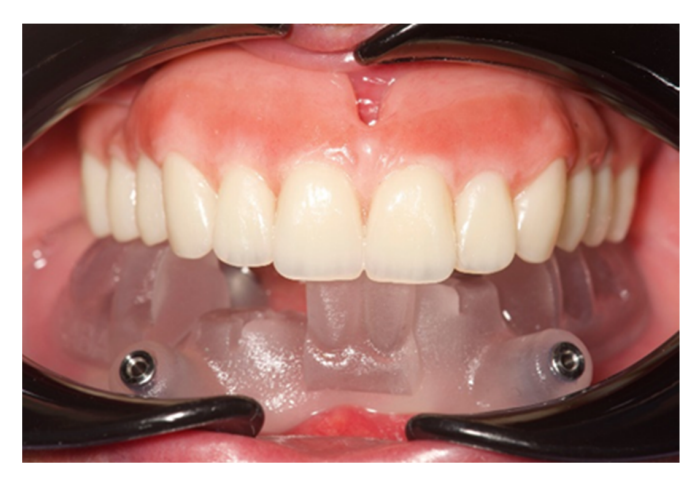

Через четыре месяца была сделана предварительная цифровая слепка функционализированного временного протеза с использованием скан-аналога для многоподдержки (Рисунки 15–17). Затем временный протез был откручен, и был подключен обычный скан-аналог. Была сделана вторая цифровая слепка положения имплантата.

Обе оттиски были выровнены с использованием небного как опорной точки (Рисунок 18). На этом этапе был напечатан эстетический пробник, который затем протестировали в ротовой полости пациента и использовали в качестве окончательной ложки для оттиска (Рисунок 19). После проверки эстетики и функции эстетический пробник был соединен с имплантатами с использованием обычных временных абатментов (Рисунок 20).

После этого эстетическая примерка была снята. Четыре новые скан-аналоги были подключены к временным абатментам и отсканированы вне рта пациента с помощью обычного экстраорального сканера (Рисунок 21). Прежде чем была изготовлена окончательная CAD/CAM конструкция, клинически и радиографически была протестирована радиопрозрачная алюминиевая конструкция. После этого было выполнено перекрестное монтаж окончательной реставрации (позиция имплантата) с функционализированной временной реставрацией, а также с оригинальным планом. На следующем приеме титановая CAD/CAM конструкция была протестирована в рту пациента. В конце концов, была доставлена фиксированная, удерживаемая винтом, имплантоподдерживаемая реставрация, изготовленная из титана, с композитом в качестве облицовочного материала (Рисунки 22–24). Композит был выбран из-за своей прочности и способности к поглощению ударов. Лингвализированный окклюзия была спроектирована для всех окончательных реставраций, с использованием анатомических зубов для верхнего протеза и модифицированных неанатомических или полуанатомических зубов для нижних протезов.